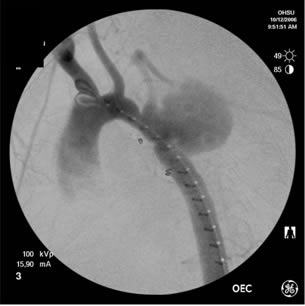

Because of the patient’s prior coarctation repairs and the morphology of the pseudoaneurysm, an endovascular repair was felt to be desirable. Based on preoperative measurements of the CT angiogram, a tapered endoprosthesis 9.5cm in length with 16mm proximal diameter and 20mm distal diameter (W.L. Gore & Associates, Inc.), originally marketed as an iliac limb, was selected for use. The patient was taken to the operating room. After induction of general anesthesia, percutaneous right femoral artery access was obtained and a measuring pigtail catheter was advanced into the distal aortic arch. An aortogram was performed which demonstrated the aortic arch and pseudoaneurysm morphology (Figure 3).